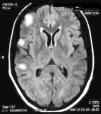

En el examen físico no había signos clínicos de actividad de LES ni de enfermedades infecciosas. El examen neurológico reveló la presencia de reflejos tendinosos aumentados en el miembro inferior izquierdo y signo de Babinsky positivo. La resonancia magnética (RM) cerebral mostró lesiones hiperintensas en T2 cortico-subcorticales en región frontal y parietal derechas que no resaltaban con gadolinio. (fig. 1). La paciente comenzó tratamiento con meprednisona 50mg/día por vía oral y fue dada de alta del hospital luego de 48 h.

El LES permaneció inactivo y la dosis de prednisona fue descendida gradualmente. En marzo del 2011 (luego de 10 meses de encontrarse neurológicamente asintomática) presenta deterioro cognitivo. Una RM de cerebro de control revela imágenes hiperintensas en T2 de las mismas características que las anteriores. Se indica un nuevo pulso de 30mg IV de gammaglobulina, sin respuesta clínica agregándose epilepsia parcial continua, en esta oportunidad en la pierna derecha. Se realiza una nueva RM de cerebro donde se agregan nuevas lesiones las cuales se vuelven bilaterales. Se decide realizar una biopsia de cerebro del lóbulo frontal derecho que informa: parénquima nervioso cortical, con incremento de la celularidad a expensas de una astrogliosis de aspecto reactivo. No se detecta vasculitis ni proliferación neoplásica. Inmunomarcación: GFAP+ CD68+NOGO A (–), P53 (–), IDH1 (–) (fig. 2).

Diagnóstico clínico del discusor (Dr. Sergio Paira)Nuestra paciente tenía las características clínicas de una ER con epilepsia parcial continua intratable y hemiparesia. Radiológicamente, lesiones córtico-subcortical hiperintensas en T2, que no resaltan con gadolinio, y evidencia histológica de inflamación cerebral. Por lo tanto, habiendo sido descartadas otras causas de EPC, asumo que la paciente presenta una ER como patología autoinmunitaria asociada a su enfermedad de base.